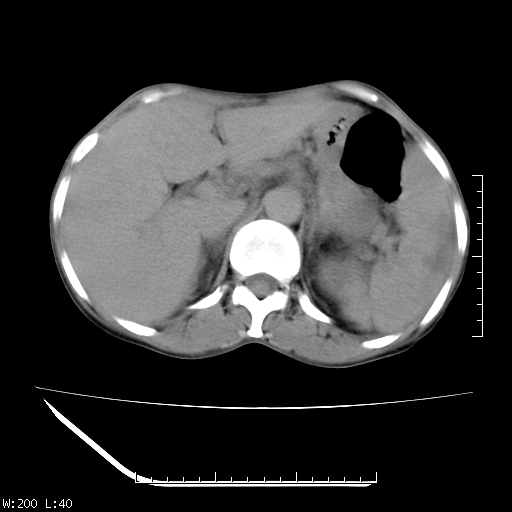

以下是引用zhangqichun5在2007-5-23 23:47:00的发言:[br]肝右叶低密度,脾低米度,左肾混杂密度,考虑是肝癌肾脾转移

以下是引用苯小孩在2007-5-24 13:30:00的发言:[br]肝、脾肿大不均匀强化,脾脏低密度区内见结节样强化.淋巴瘤?考虑为淋巴系统或血液系统疾病,建议骨穿. [br] [br]

以下是引用jsgdoctor在2007-5-24 7:53:00的发言:[br]考虑为淋巴系统或血液系统疾病,建议骨穿.